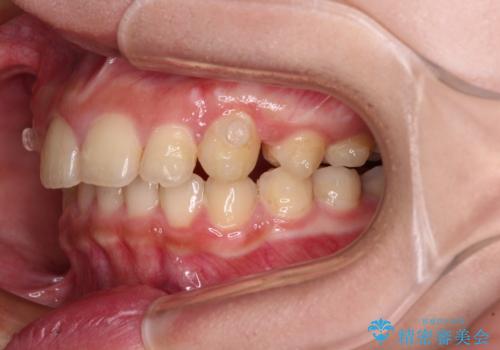

飛び出した前歯をインビザラインですっきりと

- 深い咬み合わせと上顎前歯の突出感を気にして来院された患者様です。

当院では通常、臼歯の咬合が理想的な位置に対して上顎が前方位にある場合。ワイヤー矯正または補助装置の併用したインビザライン矯正を選択しています。

今回は、できるところまででいいのでインビザライン単体で治療をしたいという希望があったため、インビザラインにて矯正治療を行うこととしました。

正面や横からの写真ではきれいに治っており、患者様は大変満足のいく仕上がりとなりましたが、深い咬み合わせの改善は不十分で、奥歯の咬み合わせも改善させることができませんでした。

インビザラインは、咬合力の強い方ですと、奥歯が歯肉内にめり込んでしまうため、前歯が強く接触してしまうことがあります。

こちらの方は、奥歯はしっかりと噛んだのですが、歯肉にめり込んでしまったことで、歯肉が腫れやすくなってしまいました。